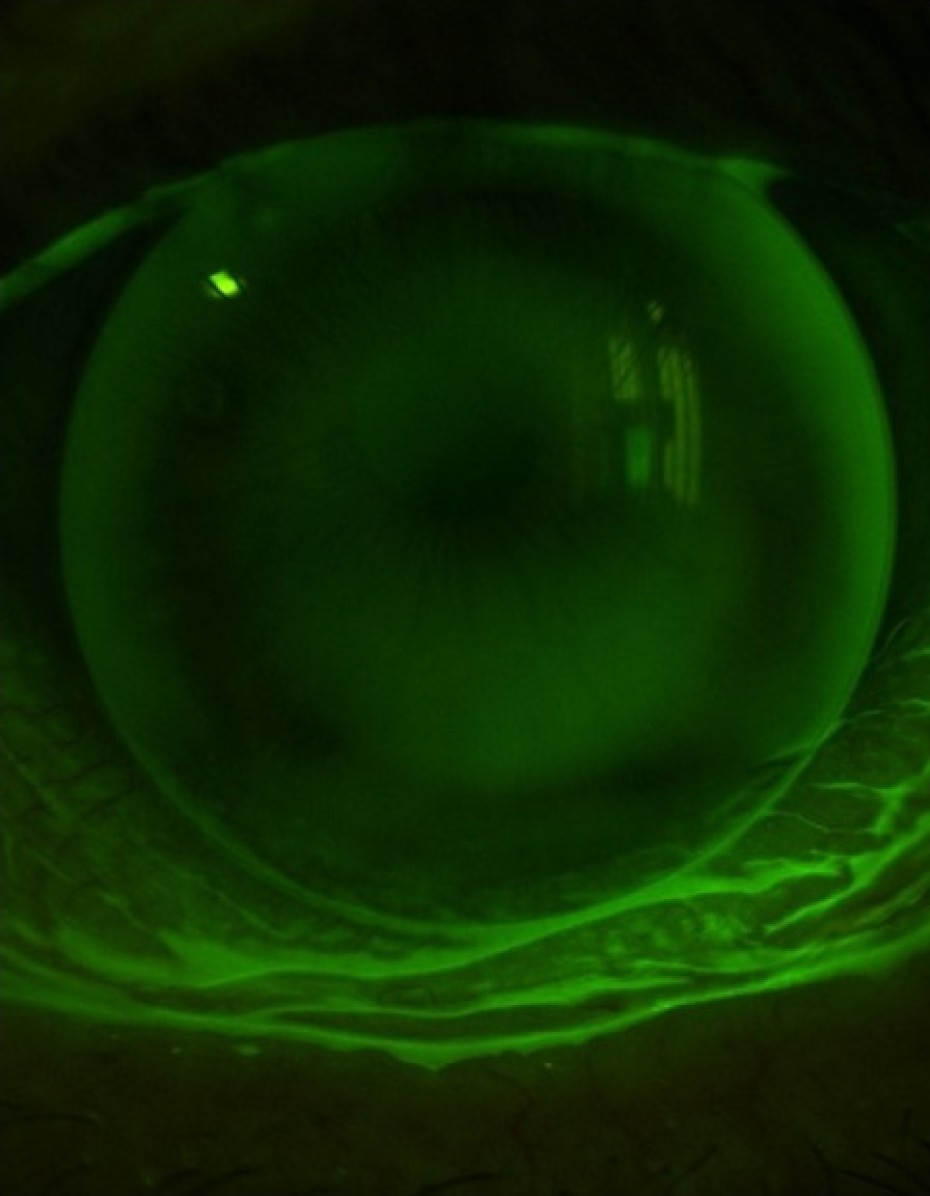

Darstellung eines Auges mit Keratokonus

KERATOKONUS-KONTAKTLINSEN

Darstellung eines Auges für Orthokeratologie

ORTHOKERATOLOGIE (ABK. ORTHO-K)

Werden Sie Ihre Kurzsichtigkeit los und zwar buchstäblich über Nacht.Das Prinzip ist ganz einfach: Sie setzen vor dem Schlafengehen die Ortho-K-Kontaktlinsen ein und tragen diese während des Schlafes. Am nächsten Morgen nehmen Sie Ihre Kontaktlinsen ab und sehen scharf.